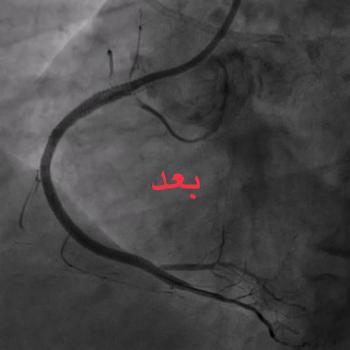

جامعة أسيوط تعلن عن نجاح فريق طبي بمستشفى القلب الجامعى بأسيوط فى علاج حالات الانسداد الكلي المزمن بالشريان التاجي باستخدام تقنية ( retrograde CTO PCI )